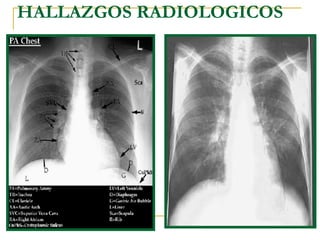

HALLAZGOS RADIOLOGICOS

FASE INICIAL Focos dispersos de opacidades en vidrio esmerilado o consolidaciones

Radiografía de tórax obtenida al ingreso (compromiso intersticial   )

Radiografía de tórax control a los 5 días del ingreso (opacidades tipo “vidrio esmerilado” )

Neumonía por  P. Carinii  en paciente VIH

Paciente VIH positivo con neumonía por  Pneumocytis carinii  (fase subaguda o en resolución)

Neumonía por  Pneumocystitis carinii.  Patrón pulmonar intersticial bilateral.

FASE AGUDA Engrosamiento de los septos alveolares

Quistes aéreos de predominio subpleural

Neumotórax por  Pneumocystis carinii  ,  (en algunos pacientes)